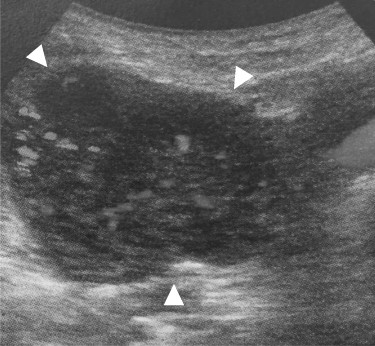

A 69-year-old woman presented to our institution with right abdominal pain. There was nothing special to mention in her family history. Her past medical history included horseshoe kidney, gastric ulcer, and asthma. Physical examination revealed a slight tenderness of the right quadrant abdomen. All laboratory parameters including the tumor markers carcinoembryonic antigen and carbohydrate antigen 19-9 were within normal limits. Abdominal ultrasonography showed a regularly shaped uniform tumor of about 50 mm in diameter that was located in the right retroperitoneum ventral to the right part of the horseshoe kidney. The tumor was hypervascularized (Fig. 1). Computed tomography (CT) showed a tumor of 80 mm in diameter ventral to the right part of the horseshoe kidney and the dorsal side of the descending part of the duodenum. On contrast-enhanced CT, the tumor showed late-phase enhancement. There were no findings of invasion into any organs and right ovarian vein ran through the tumor (Fig. 2). No metastases to organs or swollen lymph nodes were found. Magnetic resonance imaging (MRI) showed a tumor that was isointense with respect to muscle on T1-weighted images and of high-signal intensity on T2-weighted images (Fig. 3). No fatty components were detected in the tumor. Endoscopic ultrasonography showed a regularly shaped and hypoechoic tumor with no connection to the right part of the horseshoe kidney or duodenum (Fig. 4). Our working diagnosis was a retroperitoneal tumor that could be either a malignant lymphoma, leiomyoma or gastrointestinal stromal tumor.

Endoscopic ultrasonography: there was no finding of infiltration to the right kidney and the duodenum.